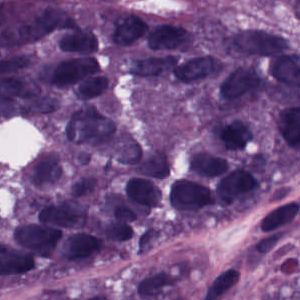

As an essential part of digital pathology, histopathology image analysis is playing increasingly important role in cancer diagnosis, which can provide direct and reliable evidence to diagnose the grade and type of cancer. This paper deals with nuclei segmentation, an important step in histopathological image analysis. The purpose of nuclei semgentation is not only counting the number of nuclei but also obtaining the detailed information of each nucleus. So unlike nuclei detection, here the outputs are the contour of each nucleus instead of only the position of their central points. Hence we can exactly extract each nucleus from the image and make it available for further analysis. For example, the features of the individual nucleus and the distribution of nuclei clusters can be used to grade and classify status of breast cancers [3, 4]. Because of appearance variation such as color, shape, and texture, nuclei segmentation from histopathological images could be very challenging, as illustrated in Fig.1, in which it is very challenging even for human to recognize and segment all nuclei within the images. Fig.1(a) and Fig.1(b) illustrate two histopathological images from different organs. Fig.1(c) and Fig.1(d) are two histopathological images from same organ but have different cancer grade.

H&E stain is the most widely used stain protocol in medical diagnosis. Typically, the nuclei of cells are stained to blue by Haematoxylin while cytoplasm is colored to pink by Eosin. But in practice, the color of H&E stained images could vary a lot due to variation in the H&E reagents, staining process, scanner and the specialist who performs the staining, as shown in Fig.1. A few H&E stain normalization methods[23, 24, 25] have been proposed to eliminate the negative interference caused by color variation. We tried two of them[23, 25] to normalize the raw H&E stained images. For our segmentation algorithm, we did not find any considerable difference between these two normalization methods. Particularly, the result shown in experiment section III is generated based on the images normalized by the method in [23]. Given a target image, this method is able to convert one image’s color into the target image’s color space based on sparse non-negative matrix factorization(NMF). We choose one best stained H&E image as the target and convert other images into its color space. According to the recommendation in [23], the hyper-parameter should be set between 0.01 and 0.1. In our experiment, is set to 0.1.